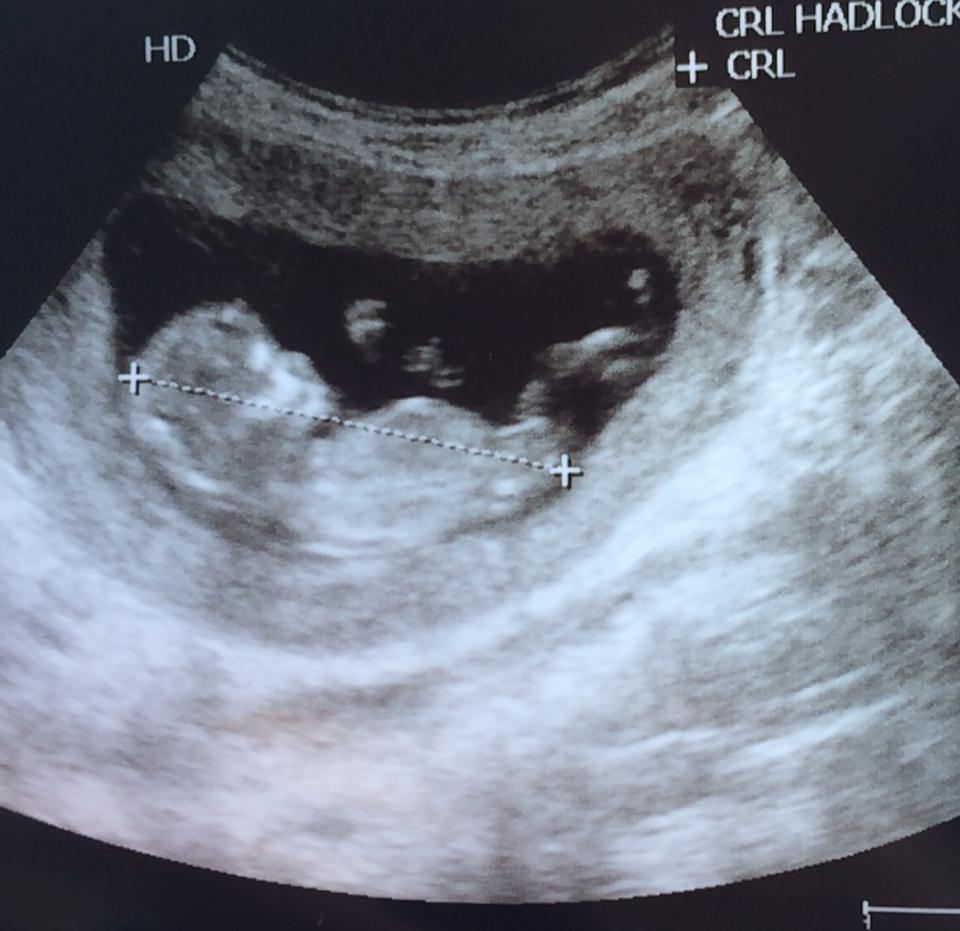

Thanks for your guesses! Baby measured at 12 week 2days in one pic and 12 weeks 3 days in a different so I'm not sure which day to use.